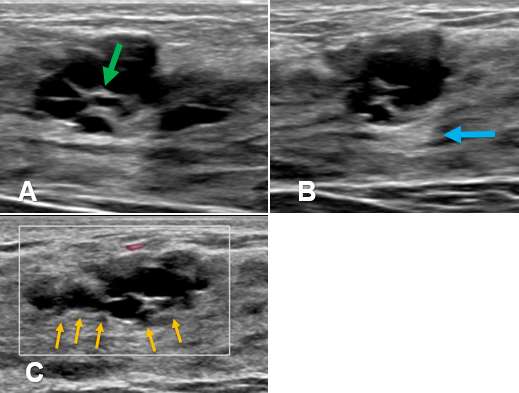

Clustered Microcyst

Clustered microcysts are an additional form of benign, fibrocystic changes that can develop in the breast. They are often encountered in peri-menopausal women which is thought to be due to prolonged exposure to progesterone as the menstrual cycle shortens.

Ultrasound - On ultrasound, clustered microcysts display features similar to simple breast They typically appear as a group of small (2-3 mm) anechoic foci with thin (<0.5 mm) intervening septa and without a discrete solid component. Clustered microcysts also demonstrate posterior acoustic enhancement, similar to simple cysts. The margins of a clustered microcyst may be microlobulated but are well-defined.